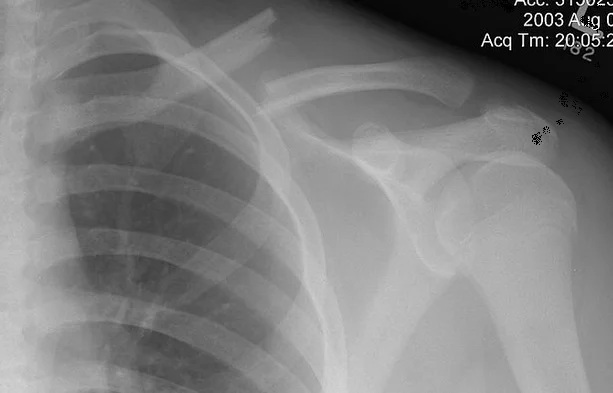

Clavicle Fracture

- Sites:

- Lateral thirds,

- Middle thirds, common (why?)

- Medial thirds

Its weakest point. The lateral fragment is depressed by the weight of the arm against trapezius, thus the shoulder droops, it is pulled medially forward by adductor function of pectoralis major causing the bone fragments to override.